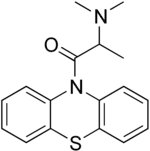

| IUPAC name

2-(Dimethylamino)-1-phenothiazin-10-ylpropan-1-one | |

| C17H18N2OS | |

| Molar mass | 298.40 g/mol |

Dimethylaminopropionylphenothiazine or 10-(alpha-dimethylaminopropionyl)phenothiazine is an antispasmodic.[1]